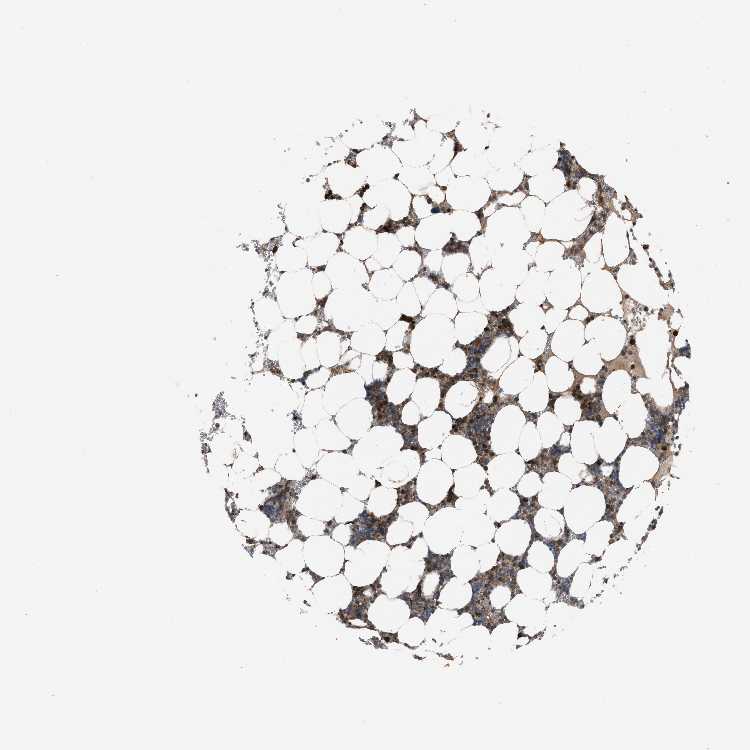

BONE MARROW - Antibody stainingi

Antibody staining in the annotated cell types in the current human tissue is reported as not detected, low, medium, or high, based on conventional immunohistochemistry profiling in selected tissues. This score is based on the combination of the staining intensity and fraction of stained cells.

Each image is clickable and will lead to virtual microscopy that enables deeper exploration of all samples and also displays staining intensity scores, fraction scores and subcellular localization as well as patient and tissue information for each sample.

Antibody HPA021197

Hematopoietic cells Medium